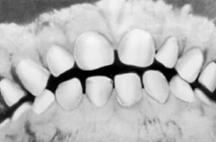

Поскольку сроки и последовательность формирования молочного и постоянного прикуса у детей достаточно определенны (таблица 2,3), их широко используют в определении « зубного возраста», который устанавливают путем подсчета числа прорезавшихся зубов и совпадения его со стандартными возрастными нормами.

Молочные зубы прорезываются с 6 мес до 2-2,5 лет и на этом отрезке постнатального онтогенеза могут служить в качестве показателя физиологической зрелости.